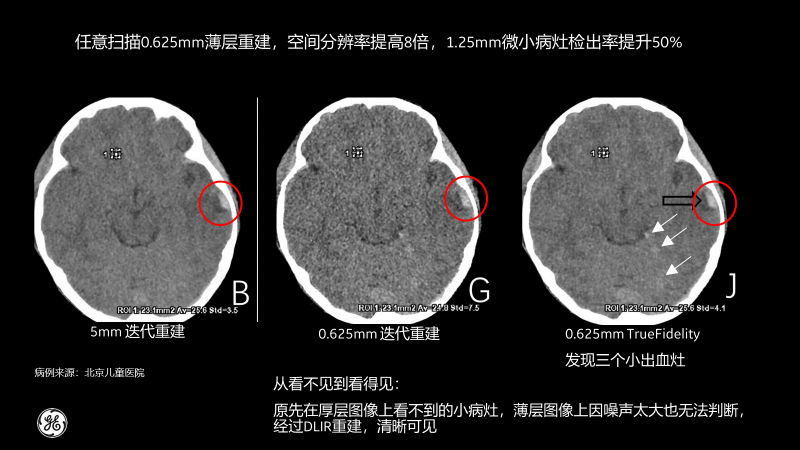

相比傳統CT圖像對腹部檢查一般都選擇5mm厚層重建,TrueFidelity可對任意體型任意部位的檢查進行0.625mm的薄層圖像重建,真實還原圖像的解剖細節和紋理,提高微小病灶的發現幾率,有助于早診早治,極大提高醫生的診斷信心。

北京兒童醫院的測試病例也顯示,經過TrueFidelity,任意掃描0.625mm薄層重建,空間分辨率能提高8倍,1.25mm微小病灶檢出率提升50%,最終額外發現了3個之前看不到的微小病灶。